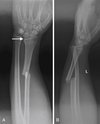

15

Q

Describe this fracture?

A

GALEAZZI

- Fracture of mid to distal radial shaft w/ dislocation of DRUJ; ligaments of inferior radioulnar joint ruptured, head of ulna displaced from ulnar notch of radius

- AIN injury

- Results from fall on outstretched hand, with wrist in extension & forearm forcibly pronated; inherently unstable, w/ tendency to redisplace after reduction

How well did you know this?